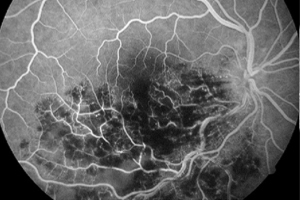

Unter einer Angiografie versteht man eine Gefäßdarstellung, mit der die Durchblutungssituation der Netzhaut beurteilt werden kann. Dies ist unter anderem wichtig bei altersabhängiger Makuladegeneration, diabetischen Netzhautveränderungen oder Durchblutungsstörungen z.B. aufgrund einer Thrombose, oder auch Tumoren.

Um die Gefäßdarstellung durchführen zu können, wird ein gelber Farbstoff in die Armvene injiziert. Anschließend werden mit einer speziellen Fotokamera Bilder von den Blutgefäßen am Augenhintergrund angefertigt. Aufgrund des in die Blutbahn gelangten Farbstoffes können die Gefäße, Gefäßverschlüsse, Gefäßneubildungen (Neovaskularisationen) und auch durchlässige Bereiche (Leckagen) gut dargestellt werden. Die fotografischen Aufnahmen ermöglichen eine genaue Darstellung der abnormen Blutgefäße oder der Größe und Lage des Gefäßverschlusses.

Die Fluoreszeinangiographie wird ambulant im Rahmen einer speziellen Sprechstunde durchgeführt.

Venenastverschluss